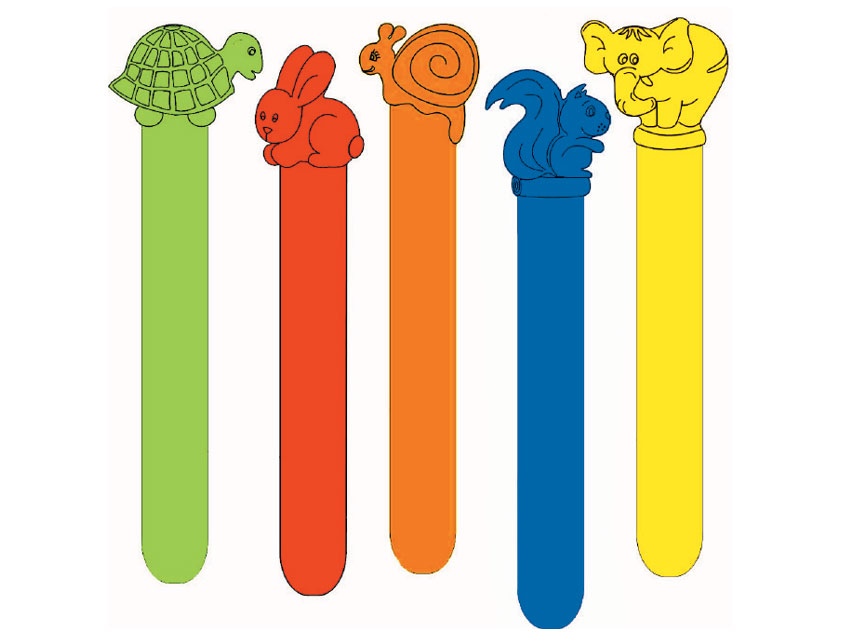

Abbassalingua

Dispositivi monouso progettati per facilitare l’esame del cavo orale e della gola, garantendo igiene e sicurezza durante le visite mediche.

All’interno sono disponibili abbassalingua utilizzati per mantenere abbassata la lingua durante le ispezioni cliniche, permettendo una visualizzazione chiara e accurata delle vie aeree superiori.

Tutti i prodotti sono selezionati per qualità, sicurezza e conformità alle normative, ideali per ambulatori, studi medici, strutture sanitarie e pronto soccorso.

Abbassalingua

Dispositivi monouso progettati per facilitare l’esame del cavo orale e della gola, garantendo igiene e sicurezza durante le visite mediche.

All’interno sono disponibili abbassalingua utilizzati per mantenere abbassata la lingua durante le ispezioni cliniche, permettendo una visualizzazione chiara e accurata delle vie aeree superiori.

Tutti i prodotti sono selezionati per qualità, sicurezza e conformità alle normative, ideali per ambulatori, studi medici, strutture sanitarie e pronto soccorso.